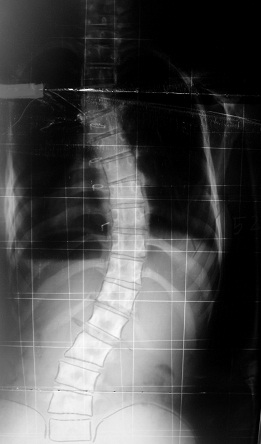

Clasificación

de los huesos:

-Largos:

Predomina la longitud (Fémur)

-Cortos:

Las tres dimensiones son similares (Escafoides)

-Planos:

La longitud y anchura predomina sobre el espesor (Escápula)

-Existen

otras formas como la radial, irregular…